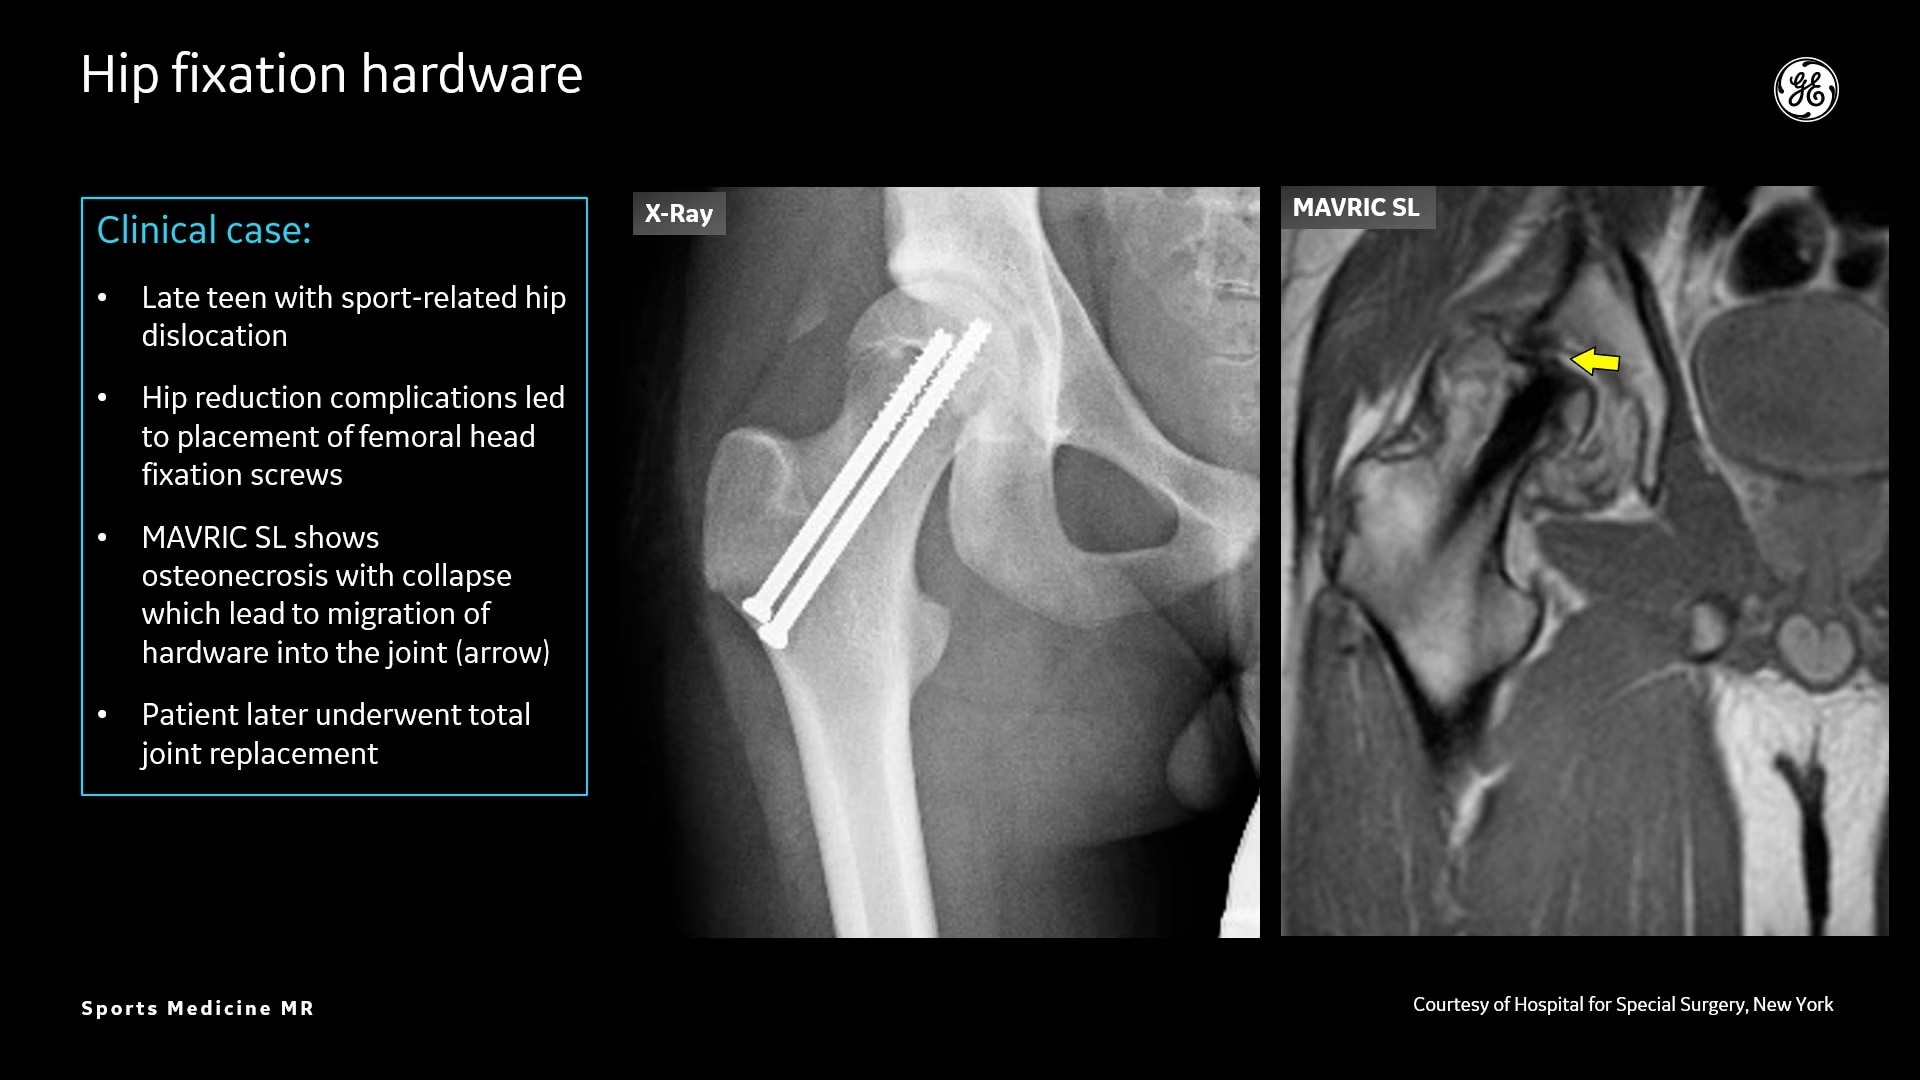

AIR Recon DL provides high-resolution images with increased SNR at markedly reduced scan times. This technology optimizes the depiction of even small injuries, such as meniscal, labral and ligament tears. The reduction in scan times increases flexibility for individually tailored MR protocols with an additional oZTEo sequence for detailed fracture assessment.

Delivering a comprehensive knee assessment in athletes

Clínica CEMTRO’s study of a complex knee injury and the use of oZTEo and AIR Recon DL.